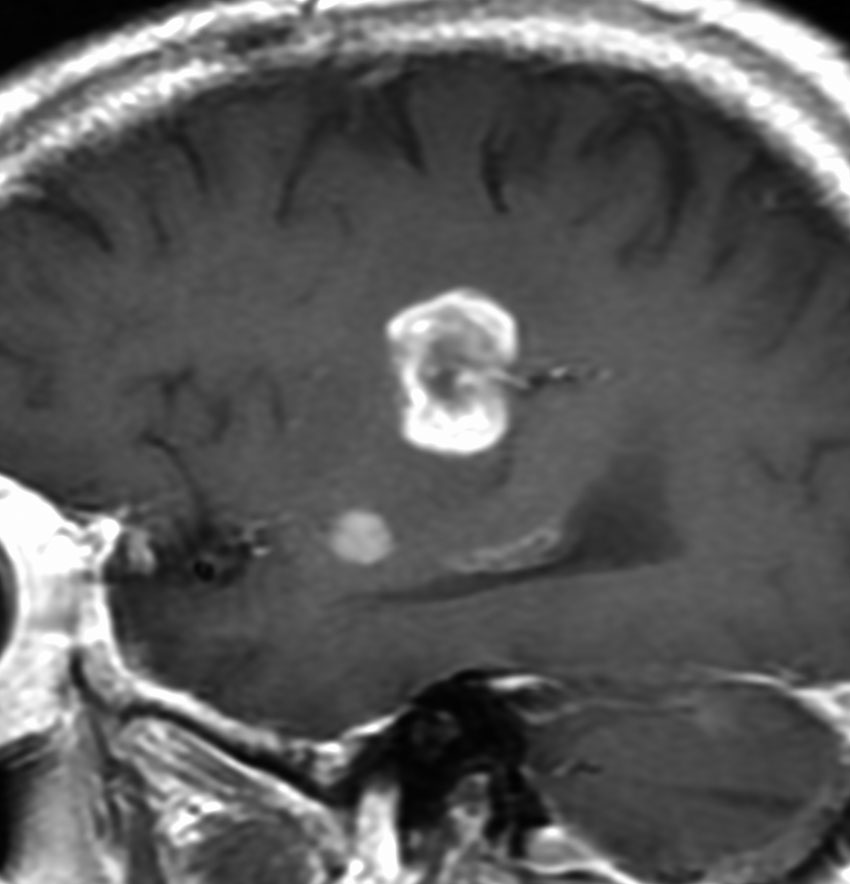

60代の患者さんの右前頭葉深部から島回に発生したものです。初発症状は症候性てんかんです。

ガドリニウム増強される腫瘍の中心部に壊死があり,悪性神経膠腫としては腫瘍周囲浮腫が強すぎるように見えるので,リンパ腫 PCNSLに似た画像所見です。

脱髄性疾患であるtumefactive multiple sclerosisに画像所見も病理所見も類似することがあります。